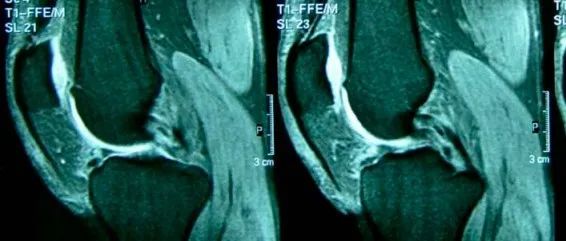

半月板是楔形的半月纤维软骨,位于膝关节的内侧和外侧股骨和胫骨髁之间。在组织学上,半月板由水和 I 型胶原纤维组成,周围环绕着弹性蛋白、蛋白多糖和糖蛋白。半月板的功能与其结构和组成密切相关。这些包括负荷传递、减震、稳定性、营养、关节润滑和本体感觉。半月板还通过增加膝关节的接触面积和一致性来降低接触应力。生物力学研究表明,作用在伸展膝关节上的大约 40% 到 60% 的负荷被传递到半月板(65%-70% 外侧和 40%-50% 内侧),并且这在屈曲时增加高达 90%。当膝关节承受负荷时,会产生压缩力、拉伸力和剪切力,其中一些会转化为环向应力...

经常会有朋友问及到半月板损伤的问题,今天膝盖君就整理一篇关于半月板损伤的详解,相信你看完之后,也对自己对状况也会有个初步了解了。半月板在哪?结构如何?半月板,位于膝关节内,是半月形的纤维软骨板,在大腿的股骨和小腿的胫骨之间, 起缓冲作用。 每个膝关节内有两个半月板,内侧半月板和外侧半月板。半月板,附着于小腿的胫骨上端,它周围部分较厚,中央部分较薄。半月板上表面接触大腿的股骨端,略凹陷,下表面接触小腿胫骨端,较平坦,从而加固球形的股骨端与较平坦的胫骨端的稳定性,使膝关节活动自如。半月板可随着膝关节运动而有一定的移动,伸膝时半月板向前移动,屈膝时向后移动。...